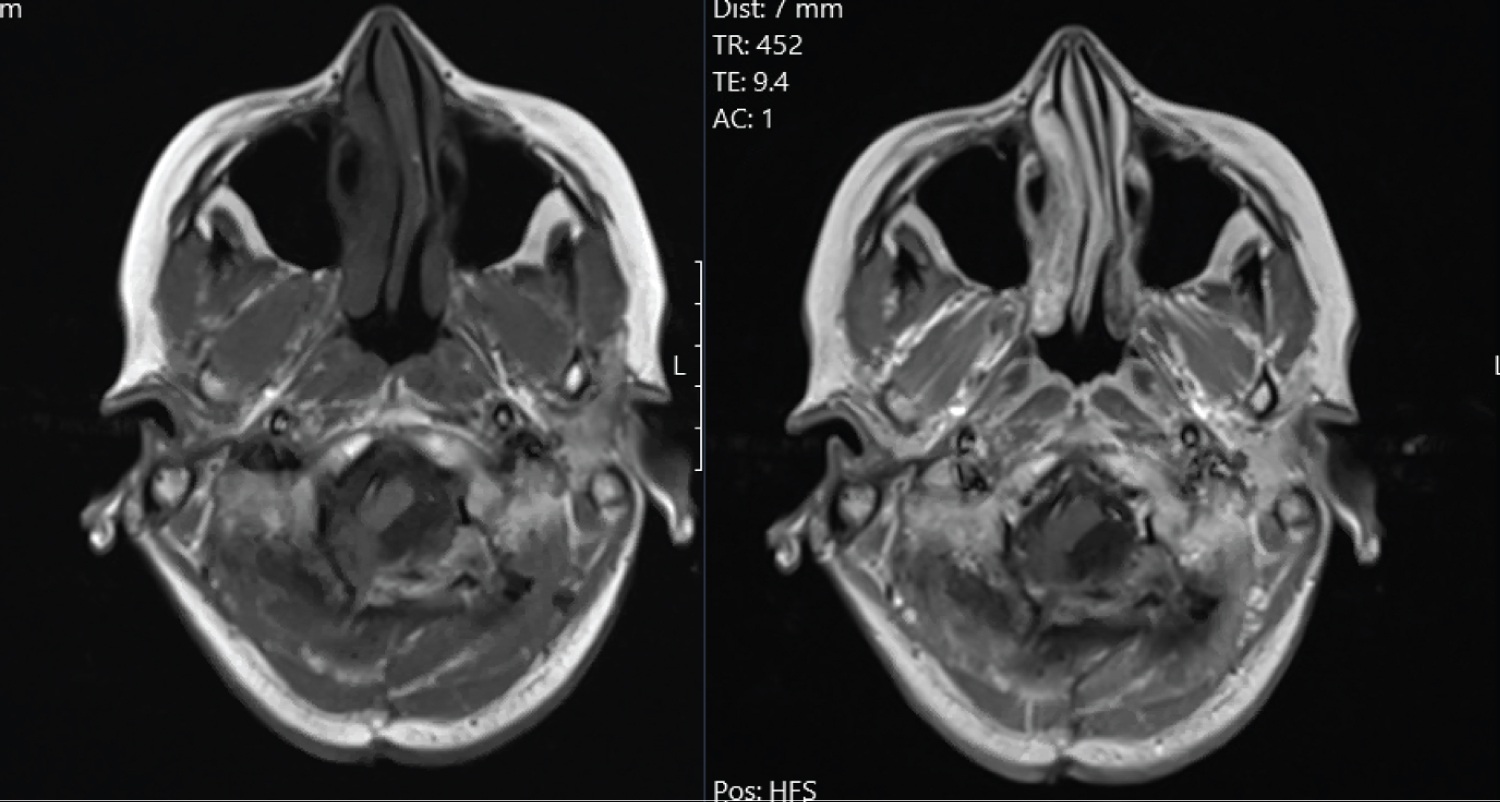

Computed tomography (CT) scan demonstrated a left sided mass at the level of the foramen magnum, measuring 23 × 16 × 22 mm, with a suggestion of brainstem compression. Magnetic resonance imaging (MRI) demonstrates a homogenously contrast enhancing intradural, extramedullary lesion, causing compression of the medulla and upper cervical spinal cord (Figure 1). Initial differential diagnoses included meningioma or nerve sheath tumour.

Figure 1: T1 MRI (non contrast scan left, contrasted right) demonstrating the contrasted, intradural, extramedullary lesion with medullary and upper cervical cord compression. View Figure 1